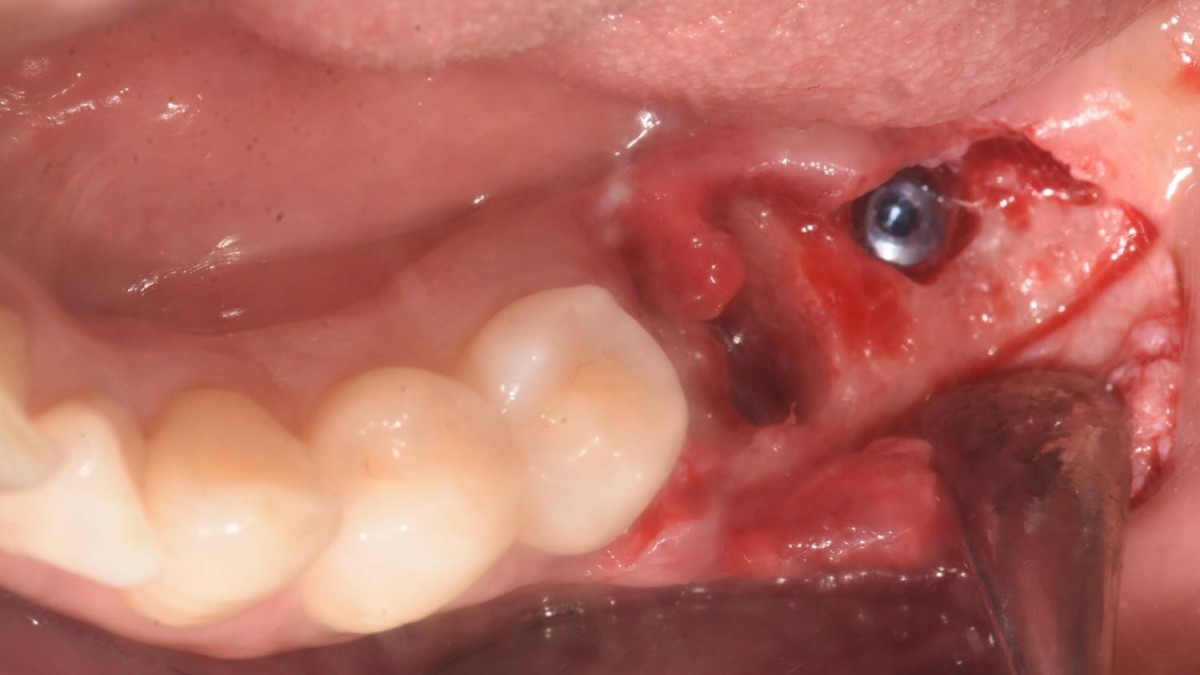

Implant in the molar zone of both jaws

A 55-year-old female patient had

bilateral problems in both jaws.

It was decided to proceed with implant-supported restoration in the left molar part first.